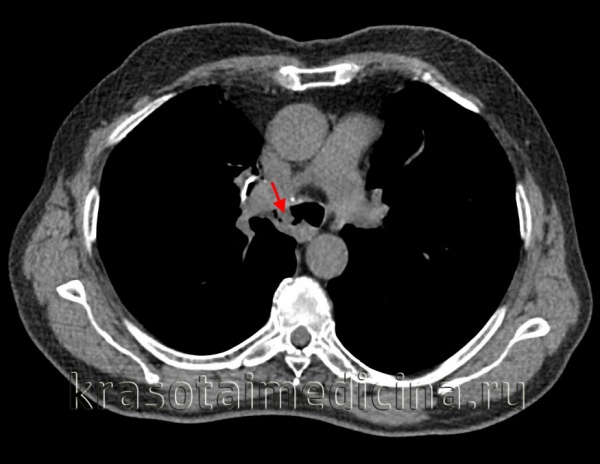

Клиническая диагностика трахеопищеводных свищей, как правило, не вызывает трудностей. Проявляются они приступообразным кашлем, который возникает во время приема пищи. Однако уточнение их локализации при рентгенологическом исследовании с барием и эзофагоскопии вызывает существенные трудности, особенно при небольших размерах свища. Более информативным оказывается трахеоскопия, при которой удается определить размеры свища, расстояние от голосовых связок и карины. Кроме того, значительную помощь в выявлении трахеопищеводных свищей оказывает также компьютерная томография.

![]() Рис.9. Компьютерная томограмма больного с трахеопищеводным свищом. | ![]() Рис. 10. Трахеоскопия больного с трахеопищеводным свищом, осложненным стенозом трахеи. |